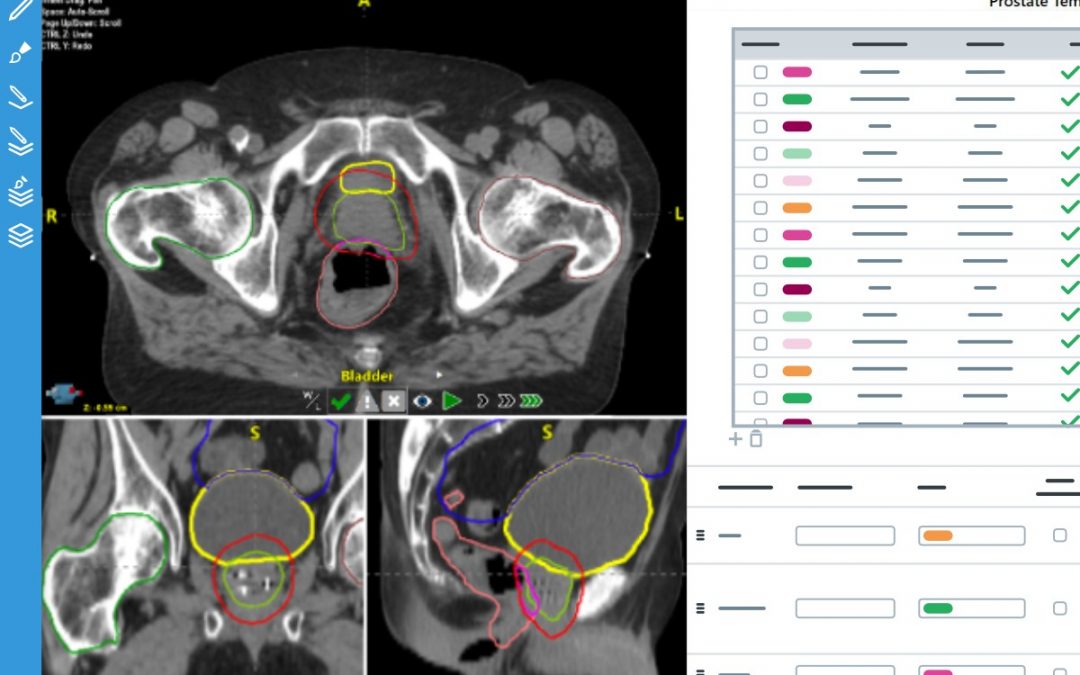

Logiciel de délinéation automatique

La délinéation, appelée « contourage » dans le jargon de la radiothérapie, est l’étape où sont modélisés les différents organes du patient dans nos logiciels de préparation du traitement. Cette étape essentielle et chronophage est effectuée par le médecin radiothérapeute grâce au scanner de simulation systématiquement réalisé avant de pouvoir débuter le traitement.

Les progrès de l’informatique permettent aujourd’hui d’automatiser, en partie, cette étape. Depuis avril 2022, nous utilisons le logiciel AutoContour proposé par la société RADformation.

Typiquement, le nombre de volumes à délinéer pour un traitement d’ORL est important. Grâce à AutoContour, il suffit de quatre minutes pour modéliser les 30 principales structures présentent sur les images.